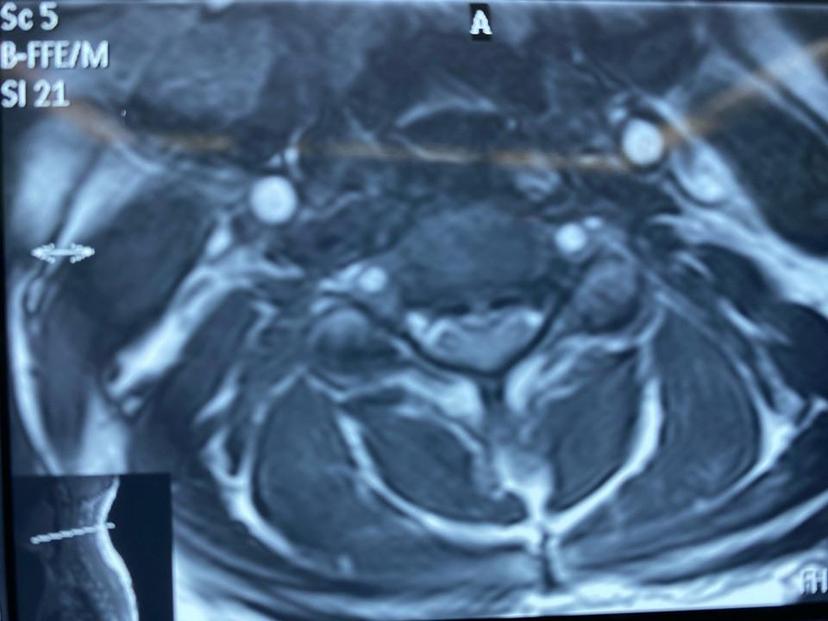

术中透视手术减压很彻底,内固定位置良好!术后第二天早上下地走路,较术前有力、稳当,矫健了很多,术后第三天出院,希望经过后期的康复训练,四肢的功能能恢复正常。